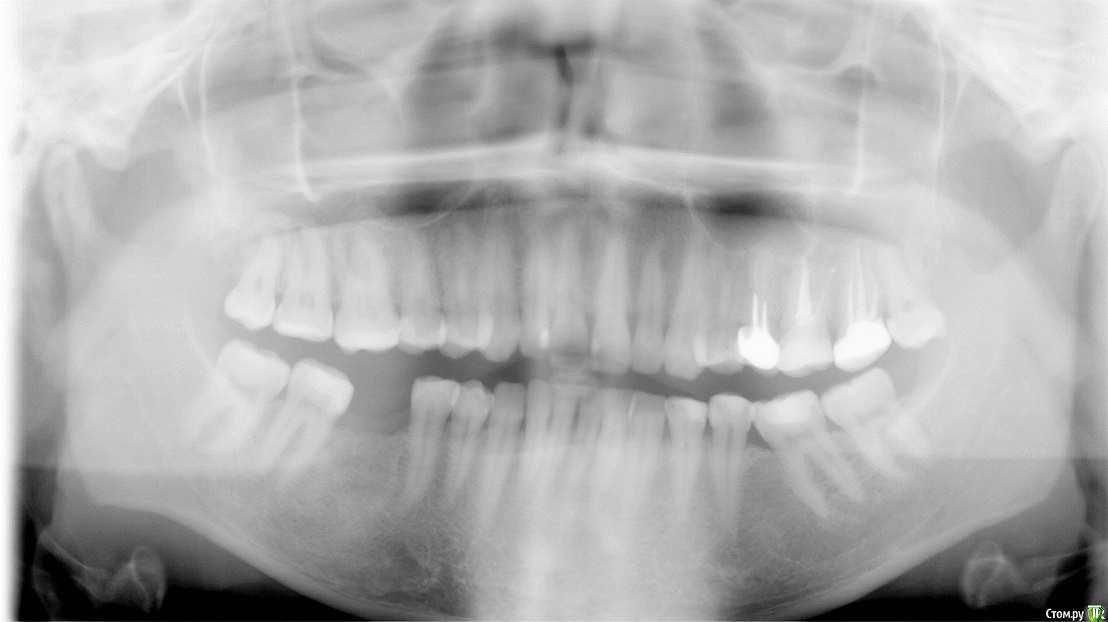

on1976 Опубликовано 18 июля, 2019 Поделиться Опубликовано 18 июля, 2019 (изменено) Добрый день!У меня огромная проблема,Я попала в чудовищную ситуацию в лечении зубов брекетами и вот это длится уже 4 года.По итогу на сегодняшний день, у меня проблемы со здоровьем, депрессия, очень изменилось лицо и прочие последствия.Случайно наткнулась на статьи о "ALF ортодонтия" и прочла об основателе ортокраниодонтии и данного метода в России Алексее Олеговиче Савинове, Skip, но найти информацию и записаться на приём я нигде не могу. А мне важно его мнение по моей ситуации. Сил моих уже больше нет лечиться поскольку улучшений нет. Помогите найти координаты и записаться на приём Савинову.Я прикрепляю файлы ренгена. Может кто выразит своё мнение. (приложенные сними на начальном этапе лечения, сейчас изменения есть, но общая картина изменилась в худшую сторону.)Ортокраниодонтия как последняя надежда! Буду благодарна если получу от вас обратную связьмой тел 89272818180e-mail: on1976@yandex.ru С уважением Сальникова Ольга. Изменено 18 июля, 2019 пользователем on1976 Ссылка на комментарий

on1976 Опубликовано 23 июля, 2019 Автор Поделиться Опубликовано 23 июля, 2019 Ортокраниодонтия - это альтернативная ортодонтия, то есть по факту - те же возможности, но другими методиками. В вашем случае прямые показания к ортогнатической хирургии. В Астрахани есть хороший ортодонт - пишите в личкуТак -то оно так, но в течении 4 лет ношения брекетов, положение стало меняться, и я задумалась о возможности решения альтернативным способом, перекос верхней части стал меньше. Возможно это можно решить ALF капой? Ссылка на комментарий